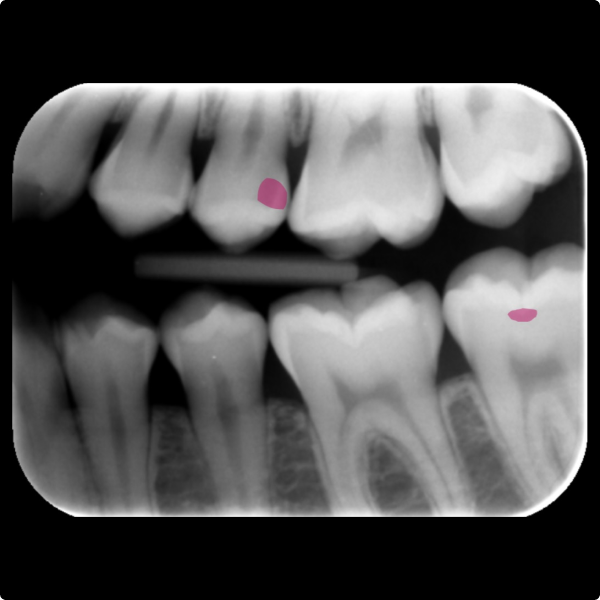

When a 17-year-old patient arrived for a routine six-month check at Dr Kiran Shankla’s practice, there were no complaints or concerns raised by the patient. During the examination a subtle colour change was observed on the upper left premolar. A bite-wing X-ray revealed a cavity, further confirmed with the aid of software.